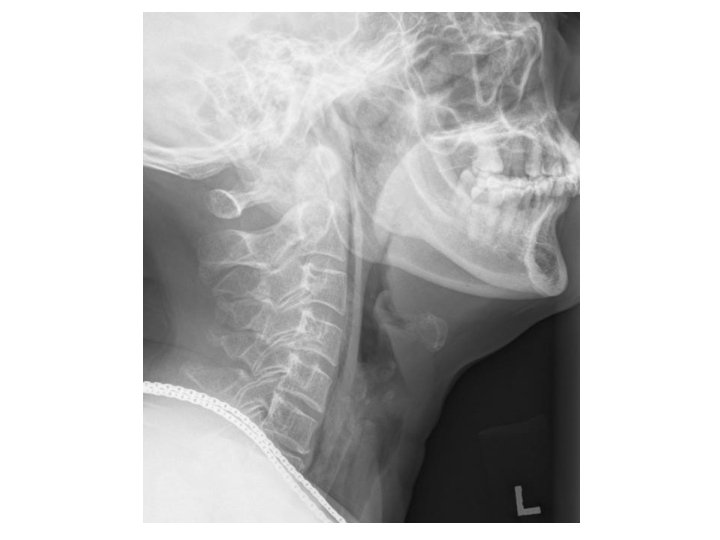

Case 1 • A 71 -year-old lady presented with left sided throat pain after fish bone ingestion. • She had attempted self induced vomiting but failed. • Afebrile, BP 127/66 P 79 • Throat: congested • Chest clear • DL: No foreign body seen

What is the abnormality? (1 mark) • Gas in retropharyngeal space • Potential space in neck, bound by ◦ Superior: skull base ◦ Inferior: fascial layers at T 2 ◦ Anterior: buccopharyngeal fascia ◦ posterior: alar fascia, a poor barrier that separates this space from prevertebral space, which continues into posterior mediastinum

Name one clinical sign you would look for (1 mark) • Surgical emphysema in neck

List two causes for the above condition (2 marks) • Traumatic – Ruptured oesophagus • Infection – Retropharyngeal abscess • Gas in retropharyngeal space can come from • Viscus: esophageal rupture, pneumomediastinum, pneumothorax, lung contusion ◦ Due to trauma, FB, vomiting • Gas forming organisms, polymicrobial with anaerobes and aerobes, infection from ◦ Tonsils, pharynx ◦ Foreign body ◦ Iatrogenic e. g. dental procedures

What is shown on the CT film? (1 mark) • Surgical emphysema along pre-vertebral plane extending into superior mediastinum